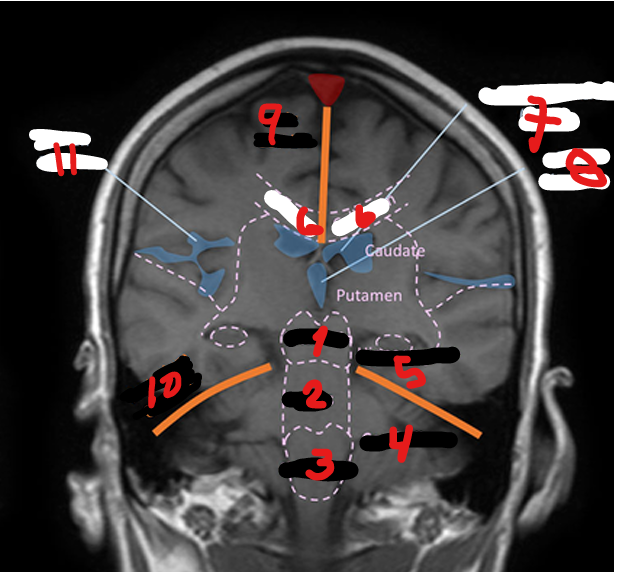

1

<p>1</p>

57

PONS

2

<p>2</p>

MEDULLA

3

<p>3</p>

CEREBELLUM

4

<p>4</p>

HIPPOCAMPUS

5

<p>5</p>

CORPUS CALLOSUM

6

<p>6</p>

LATERAL VENTRICLE

7

<p>7</p>

THIRD VENTRICLE

8

<p>8</p>

FALX CEREBRI

9

<p>9</p>

TENTORIUM CEREBELLI

10

<p>10</p>

SYLVIAN FISSURE

11

<p>11</p>